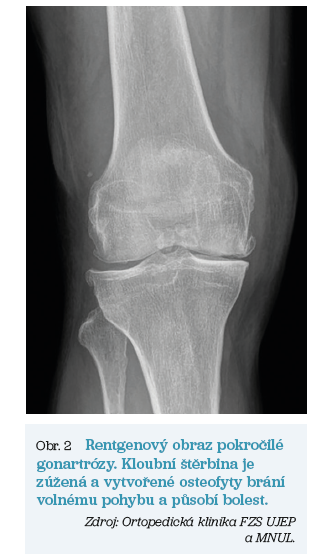

V obou případech však dochází k postupnému opotřebení kloubní chrupavky, ke zužování kloubní štěrbiny, tvorbě kostních výrůstku (tzv. osteofytů) a v nejzazších fázích až k nekróze kostní tkáně. Pomocí rentgenových snímků lze tyto artrotické změny vizualizovat. Základní anatomii a rozdíly mezi zdravým kloubem a kloubem postiženým artrózou ukazují obrázky 1 a 2.

Artróza kolenního kloubu je zdaleka nejčastější indikací k výkonu TEP. Jedná se o onemocnění, na jehož vzniku se podílí více faktorů, a to zejména věkem podmíněná degenerace, dlouhodobé přetěžování kloubu, genetické predispozice a další. Artróza sekundární pak může být důsledkem předchozích operačních výkonů, zlomenin femuru a/nebo tibie, vrozených vývojových vad nebo například prodělaných kloubních zánětů. Zkrátka je tedy známa určitá konkrétní příčina vzniku či zhoršení kloubních obtíží.